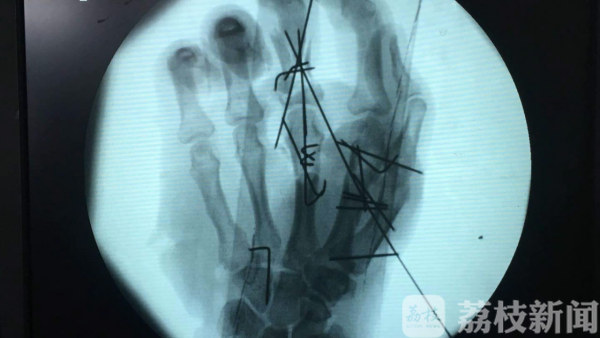

柏大爷被推进手术室进行局部麻醉后,医生对患者清洗伤口,更加细致的检查了伤口,受伤左手手指明显变形,手背大部分皮,左手背约7*8cm的大片皮肤软组织被机器撕脱,且撕脱的皮肤已经破碎,第2-4指掌指骨粉碎性骨折,夏主任立即与团队制定出了手术方案,手术分两次进行,手术从上午进行到了下午,将患者的碎骨一块一块的接上,终于将患者的5个手指全部接上。手术保住患者的左手指,之后根据病人的恢复情况再进行第二次皮瓣手术。万幸的是,经过医生团队近5个小时努力合作,帮助患者保住了左手!